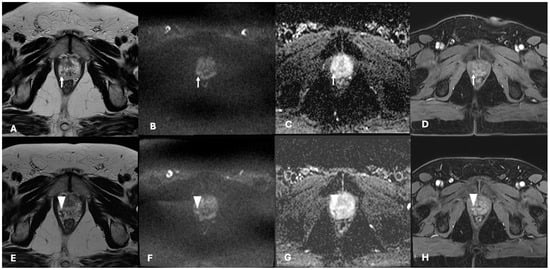

3.3. Oncological Outcomes